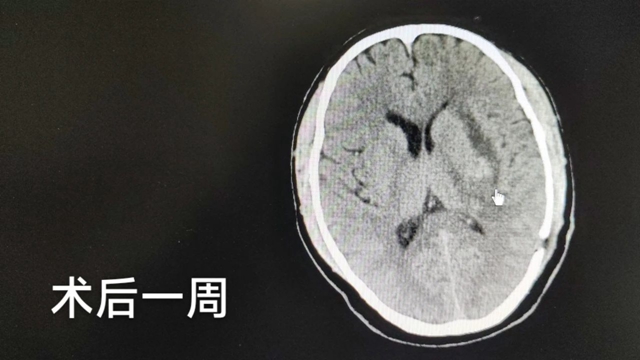

术后3天,就拔除了血浆引流管,予以中西医结合康复治疗,张老师恢复良好,神志清楚且精神状态良好,GCS 评分15分,右侧肢体肌力3-4级,尚在继续康复训练中......

患者检查影像结果